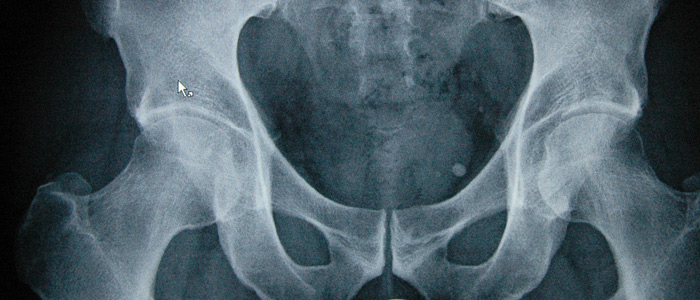

Digitales Röntgen

Neue Diagnoseverfahren wie z.B. Ultraschall oder Kernspintomographie können nur teilweise helfen, auf eine Röntgenaufnahme zu verzichten. Das konventionelle Röntgenbild stellt nach wie vor die wichtigste Basisdiagnostik dar.

In unserer Praxis setzen wir ein digitales Bildverarbeitungssystem der Firma Fuji ein, das jederzeit eine optimale Bildqualität liefert und außerdem die Strahlendosis reduziert.

Diese Untersuchungsmethode ist durch eine hohe Präzision gekennzeichnet und gilt heutzutage als Goldstandard. Messorte sind die Wirbelsäule und der Oberschenkelhals.